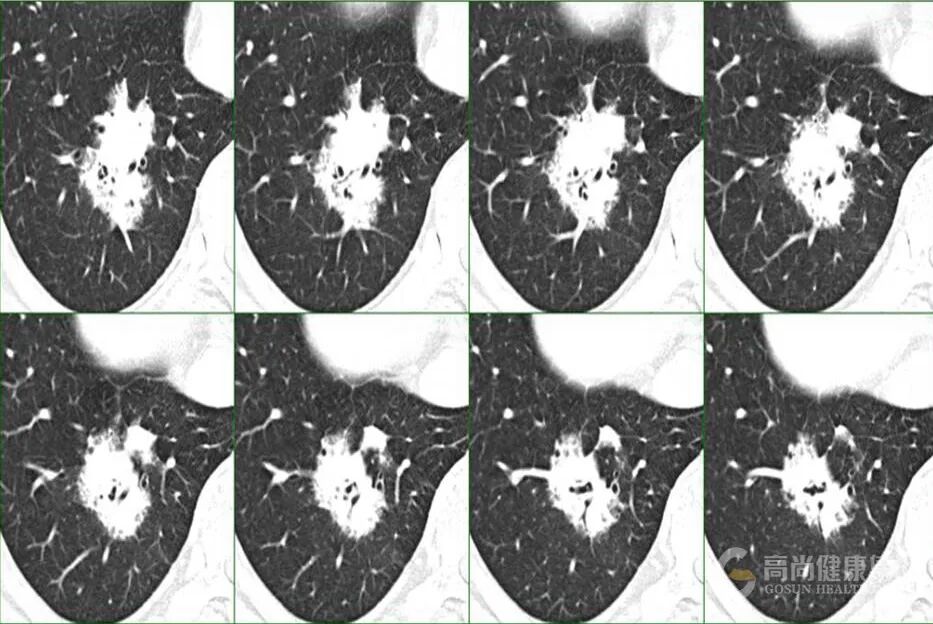

1、单一肺内病灶最主要是判断病变的性质,虽然比较像肿瘤,但仔细看病变内除了有支气管充气影,还有气泡影,病变局部边缘也有点模糊,因此这个炎症(脓肿)是有可能的,这个人肺泡灌洗出现克雷伯杆菌,结合病史那克雷伯肺炎(脓肿)是有可能的。

4、PPL 肿块型是有可能,内支气管扩张伴僵硬?

7、MALT 有可能,代谢上比较符合,病灶境界较清楚,周围还算干净,渗出不明显,支气管局部狭窄,患者无明显症状,就是 PPD 试验强阳不知怎么解释,不会是两者合并存在吧。

9、孤零零一个病灶,主要围绕气管生长,所示支气管基本通畅。有钙化,病灶整体密度偏高,病灶周围有少许磨玻璃,总体感觉偏向感染性病变,或者在已有病变 (如淀粉样变性什么的 (的基础上发生的感染,具体什么感染,结合临床,不象常见的,真菌放线菌等少见的要考虑下。

10、支气管迂曲扩张,考虑肺腺癌。

12、没有临床症状,单看影像,不看实验室检查结果的话,是比较像肺 MALT 的。

MALT 的支气管扩张并无支气管管壁的破坏。由于淋巴瘤组织浸润导致肺泡塌陷,支气管周围实质破坏造成的,这类支气管扩张在肿瘤治疗后有时可消失。

结节、肿块,边缘模糊

充气支气管粗大、扭曲

▼伴有空气支气管征充气的支气管粗大、扭曲;